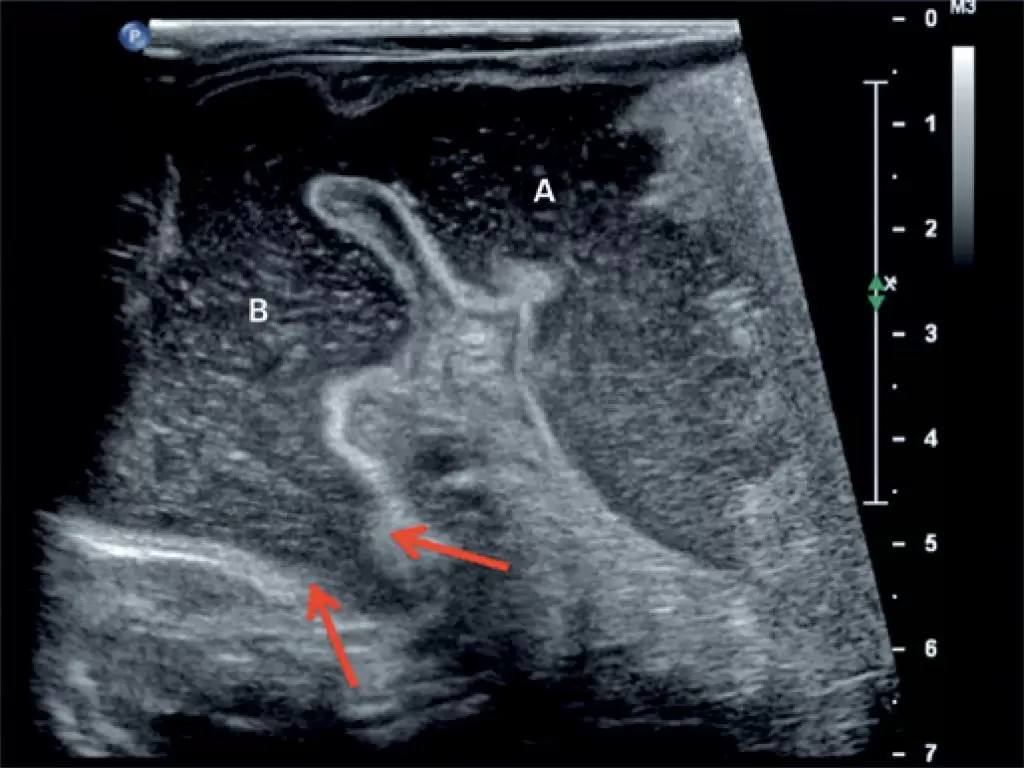

Episódios de vômito em recém-nascidos são extremamente comuns e frequentemente atribuídos a refluxo gastresofágico. Os sintomas de vômito, no entanto, podem ser causados por outras complicações. Neste relato, apresentamos dois casos: um lactente masculino, com 1 mês de idade, e um feminino, com 2 meses, ambos apresentando episódios de vômitos que levaram à desnutrição. Alguns pediatras costumam atribuir o diagnóstico de refluxo gastresofágico a recém-nascidos que estão vomitando; mas parcela da população tem outras causas que levam a sintomas semelhantes. O pediatra deve estar atento aos sinais clínicos de perda de peso, desidratação e desnutrição, para investigar outras causas de vômitos.